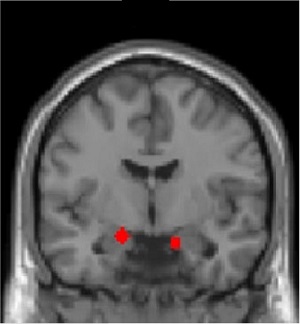

The amygdala, a brain area involved in associative learning, value encoding, and emotional responses, was particularly important. Both smaller amygdala volume and less precise tracking of the negative value of the face stimuli in the amygdala independently predicted PTSD symptom severity. Differences in value tracking and associability were also found in other brain regions involved in computation related to threat learning, such as the striatum, the hippocampus, and the dorsal anterior cingulate cortex.

Regions of interest used in the computational imaging analysis (the amygdala, defined functionally, is shown in red). Source: Nature Neuroscience, Dr. Schiller, Dr. Harpaz-Rotem.